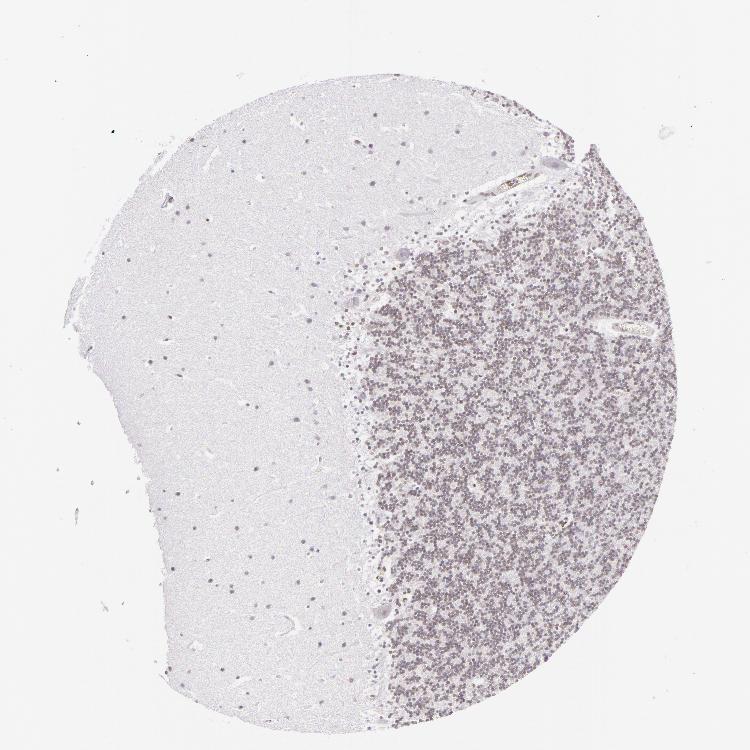

CEREBELLUM - Antibody stainingi

Antibody staining in the annotated cell types in the current human tissue is reported as not detected, low, medium, or high, based on conventional immunohistochemistry profiling in selected tissues. This score is based on the combination of the staining intensity and fraction of stained cells.

Each image is clickable and will lead to virtual microscopy that enables deeper exploration of all samples and also displays staining intensity scores, fraction scores and subcellular localization as well as patient and tissue information for each sample.

Antibody HPA000609Antibody CAB001545Antibody CAB002029Antibody CAB062552

Purkinje cells Not detectedNot detectedNot detectedNot detected

Cells in granular layer Not detectedNot detectedNot detectedNot detected

Cells in molecular layer Not detectedNot detectedLowNot detected